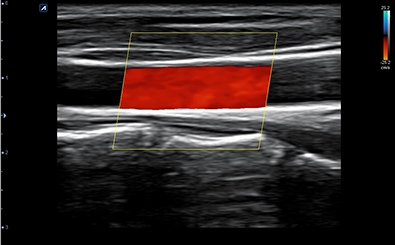

CLINICAL IMAGES

臨床影像

Carotid Artery

Carotid Artery